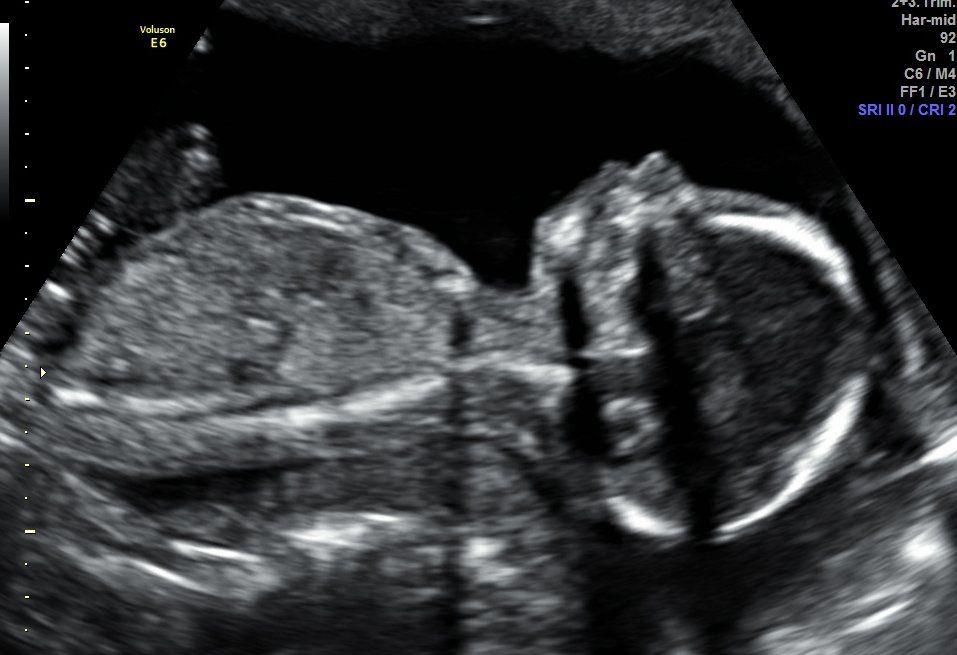

Imagen 8K ¿Qué es? La imagen 8K es una técnica novedosa que aporta mayor sensación de realismo a las imágenes que se obtienen mediante la adquisición de ecografía 5D que, ya de por sí, resulta ser una técnica ecográfica hiper-realista. Dicha técnica suaviza y texturiza las imágenes obtenidas, aumenta los contrastes y se incorporan detalles que aumentan, si cabe, la sensación de realismo. A petición del cliente la imagen seleccionada es procesada y entregada durante los días posteriores a la realización de la ecografía 5D. En Centre Miramed estamos orgullosos de poder poner a disposición de nuestros/as clientes/as la técnica 8K como ejemplo de vanguardia y crecimiento continuado.